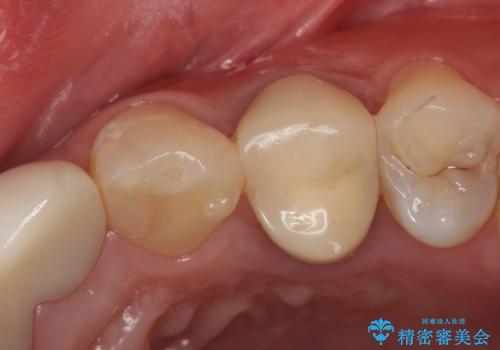

歯ぐきの深い位置まで虫歯が 歯周外科→被せもの による奥歯の治療

多発した縁下カリエス 歯周外科を併用する虫歯治療